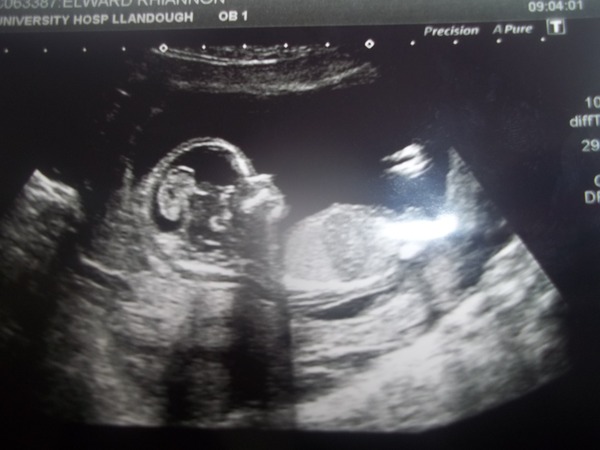

RhiannonElward · 07/04/2015 12:03

Also, I had my 12 week scan today, and all is well with little one, there are pictures on the facebook page if anyone hasn't noticed :)

Can;t get onto FB at work Rhiannon, but YAY! how exciting!! Any date change? x

Hang on Kato, here's one for you then. I had my date moved forward a day, so I'm die on the 12th (a nicer number than 13th so I'm pleased about that haha)

I am not die on the 12th, unless something unexpected happens, but I am due then instead.

wow what a beautifully clear scan pic. Lovely!

Wow thats a belter! So clear! I'd be happier with a 12 than a 13 too. And I'd rather not die either! Hope you have nice plans for the rest of scan day!

Lovely scan pics on fb rhi! My scan day is the day after tomorrow- v excited but also pretty nervous. I don't have the day off unfortunately dulcet- I work over the road so I'm literally starting work at 8, leaving at 8.30 for the scan at 9, then going straight back again after.